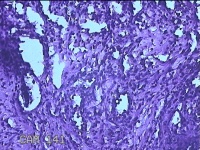

右侧手掌肉芽组织

性别

女

年龄

48岁

临床诊断

手掌开放性损伤

一般病史

右侧手掌肉芽组织增生

标本名称

大体所见

灰白暗红色带皮肤样组织1.3x0.8x0.3cm一块,切面灰白粉红色,质软。